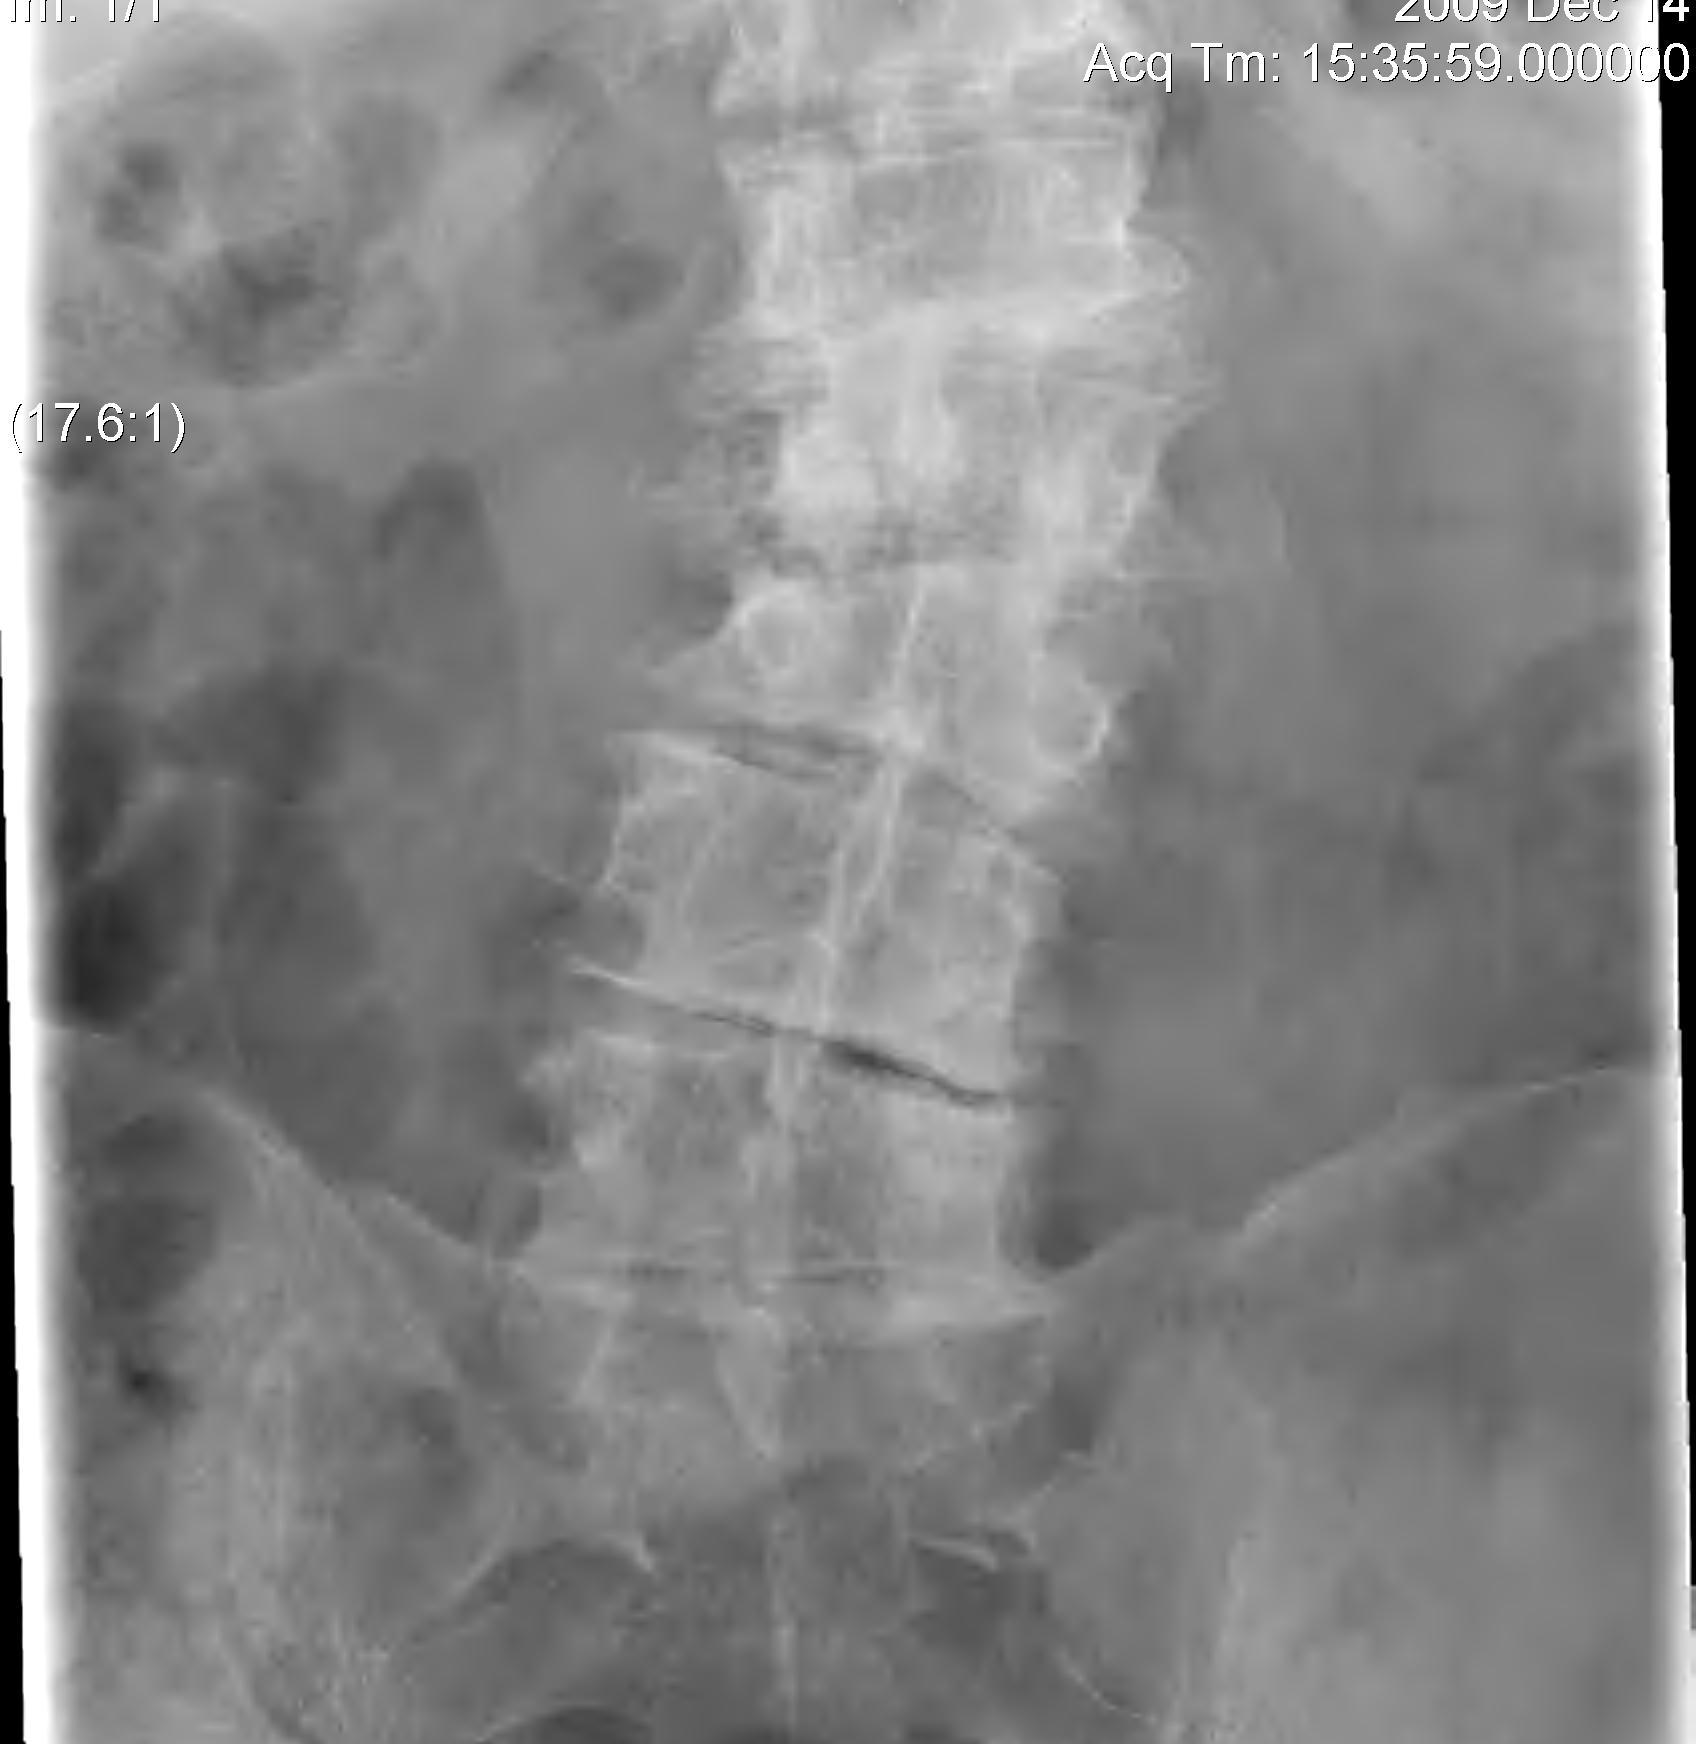

X-ray